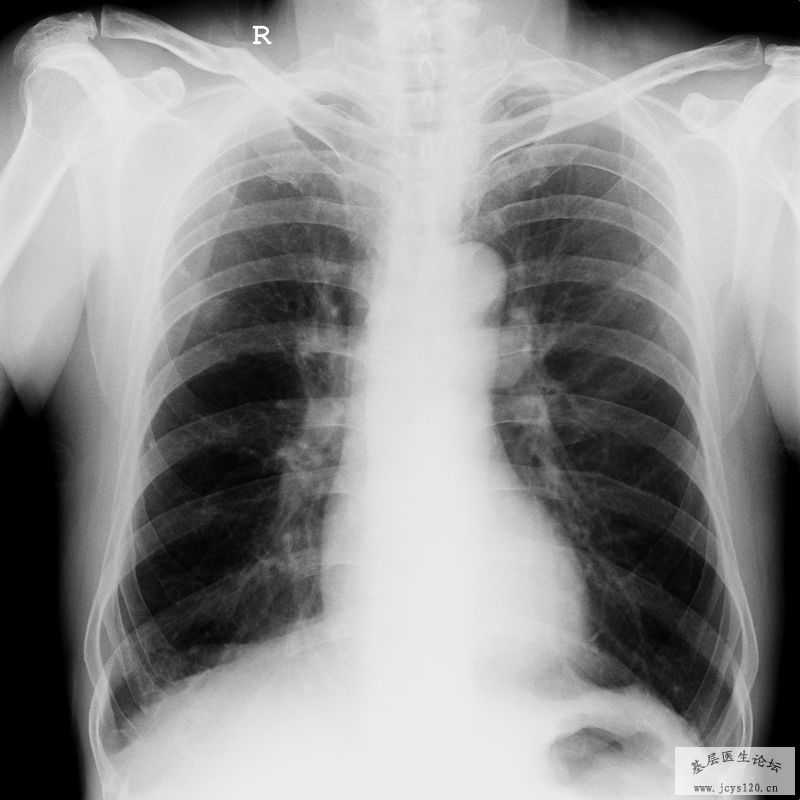

同行帮给看一下这个造影,需要怎么治疗比较理想